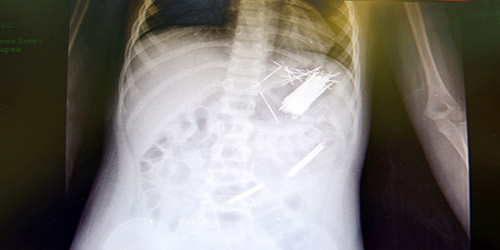

تمكَّن فريق طبي بمستشفى أبها للولادة والأطفال بقيادة الدكتور عادل محيي الدين الشهراني من استخراج عدد (50) دبوسًا للشعر من معدة طفل، يبلغ من العمر سبع سنوات، وذلك عن طريق جراحة المنظار. وقد استغرقت العملية ثلاث ساعات، وتم نقل المريض لجناح التنويم بعد إجراء العملية بدون أي مضاعفات - ولله الحمد -. أوضح ذلك المتحدث الرسمي لصحة المنطقة سعيد بن عبد الله النقير.